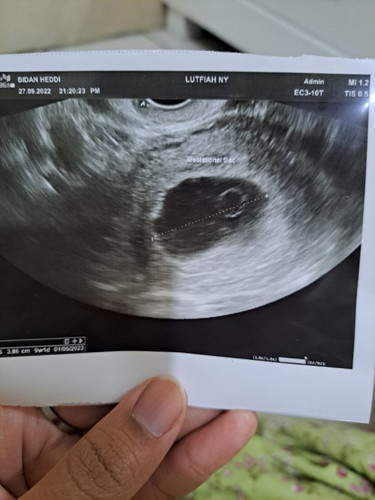

itu di dalam kantung yolk sac ya bun, bakal plasenta ?

kalo yolk sac jarang bun kehamilan nya berkembang ke tahap selanjutnya, karena dia seharusnya mengikuti embrio dulu, tapi semua itu kembali lagi ke pencipta bun, bagi tuhan gada yg mustahil, bunda berdoa aja terus kalo bisa dibawak tahajud, karena biasanya kalo udah ada yolk sac seharusnya sudah ada embrio dengan usia yg sama dengan yolk sac nya, semoga bunda dapat mukjizat dari allah ya diberi kehamilan yg sehat normal sempurna aamiin

kynya itu masih bisa bertahan de bun soalnya ada yok sacnya, klo aku belum ada bun, tggu aja dulu, klo emang blom rezeki bakal ada tanda kok ky pendarahan dll, tetep di pertahanin dulu bun